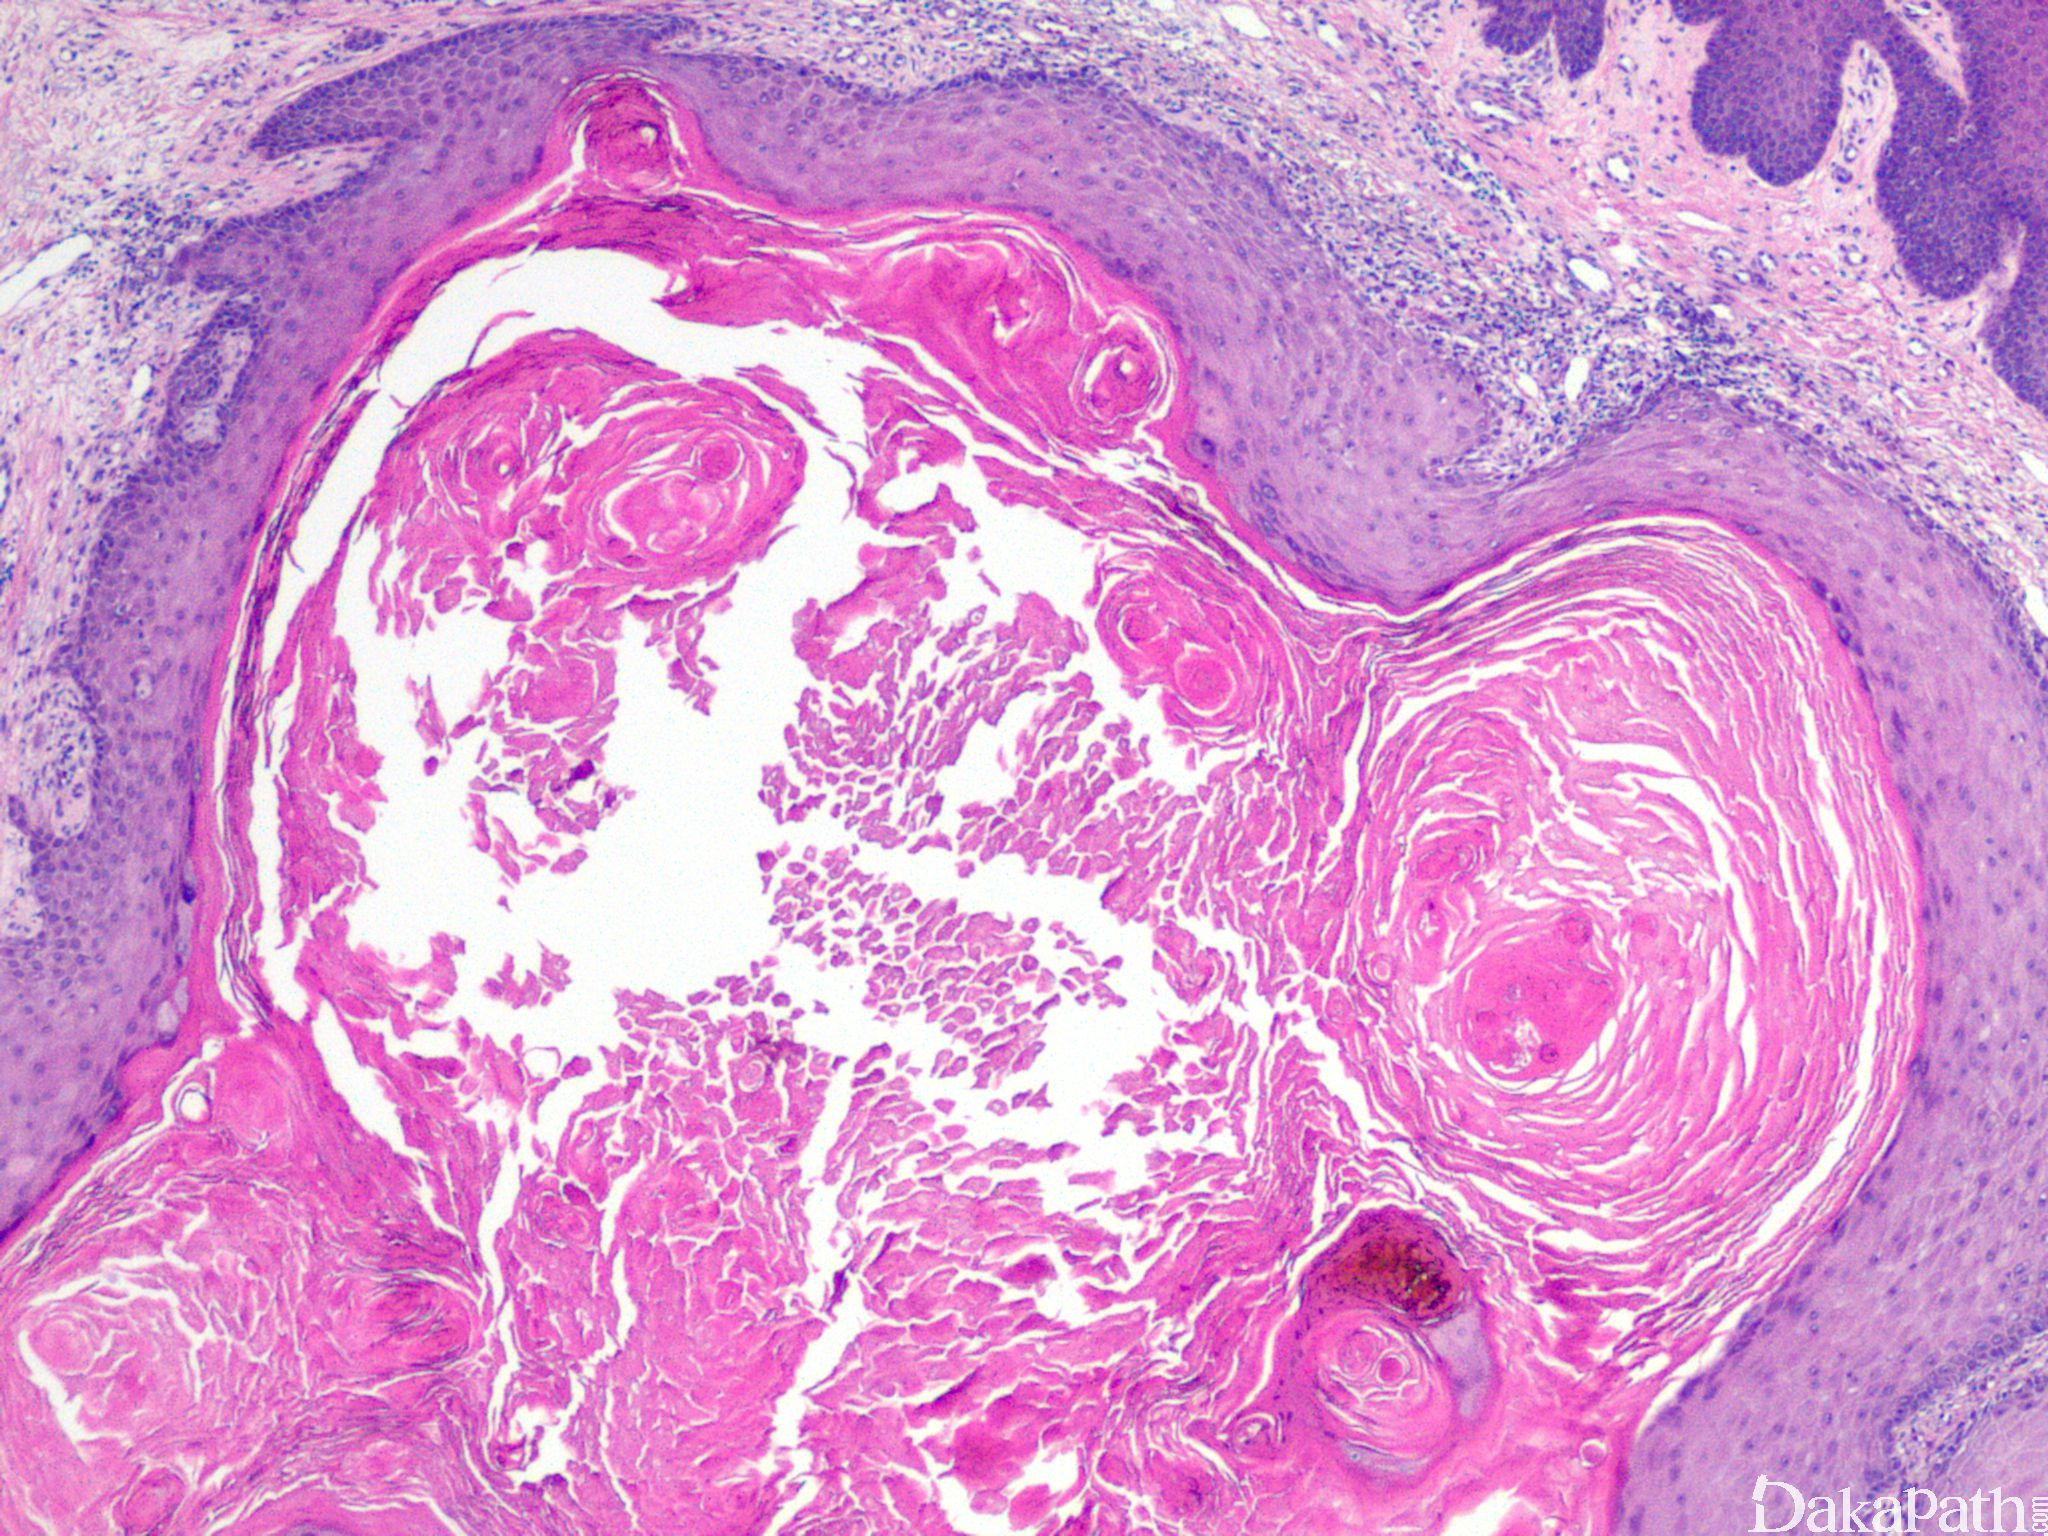

皮肤鳞状细胞癌

Squamous cell Carcinoma

细胞异型轻重不一,分化程度不等,可分为高分化、中分化及低分化

高分化者细胞仅轻到中度异型,往往具丰富的嗜酸性胞质,角化现象明显;

中分化癌介于两者之间,至少部分显示可识别的角化;

根据组织形态不同也可分为:棘层松解型、角化棘皮瘤型、透明细胞型、湿疣状鳞状细癌、疣状鳞状细胞癌、梭形细胞型、促纤维增生性等多种类型。